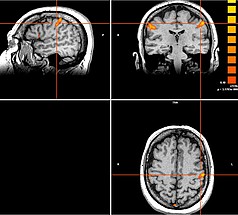

Neben den Bewegungsstörungen sind mittlerweile auch einige neuropsychiatrische Erkrankungen, wie die Depression oder Zwangsstörungen bekannt, bei denen fehlerhafte Hirnareale durch die Tiefe Hirnstimulation verändert (=moduliert) werden können. Bei schweren therapieresistenten Verläufen kann auch hier dieses Verfahren angeboten werden.

Neben den Bewegungsstörungen sind mittlerweile auch einige neuropsychiatrische Erkrankungen, wie die Depression oder Zwangsstörungen bekannt, bei denen fehlerhafte Hirnareale durch die Tiefe Hirnstimulation verändert (=moduliert) werden können. Gemeinsam mit dem ZI Mannheim erforschen wir neue Zielstrukturen und Indikationen.